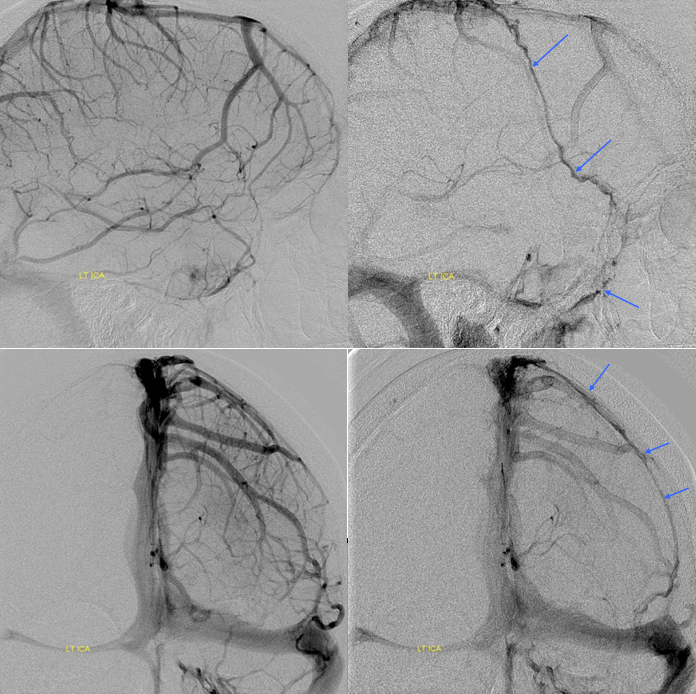

The general neurosurgical fact that the anterior third of the superior sagittal sinus can be safely sacrificed is true almost all the time. When it is not, consequences can be catastrophic. Normally, few veins drain into the anterior 3rd of the SSS, and these usually have collaterals. However, occasionally a large frontal or sylvian vein happens to drain anteriorly. Taking this sinus means risking a venous infarct. Here is an extreme example of dominant inferior left frontal vein draining into the anterior third of the frontal sinus, on MRI. Case courtesy Dr. Howard Riina

Angio is much easier to appreciate. It is well to learn how to spot these veins on MR or CT, as most patients don’t get presurgical angiography for nonvascular lesion